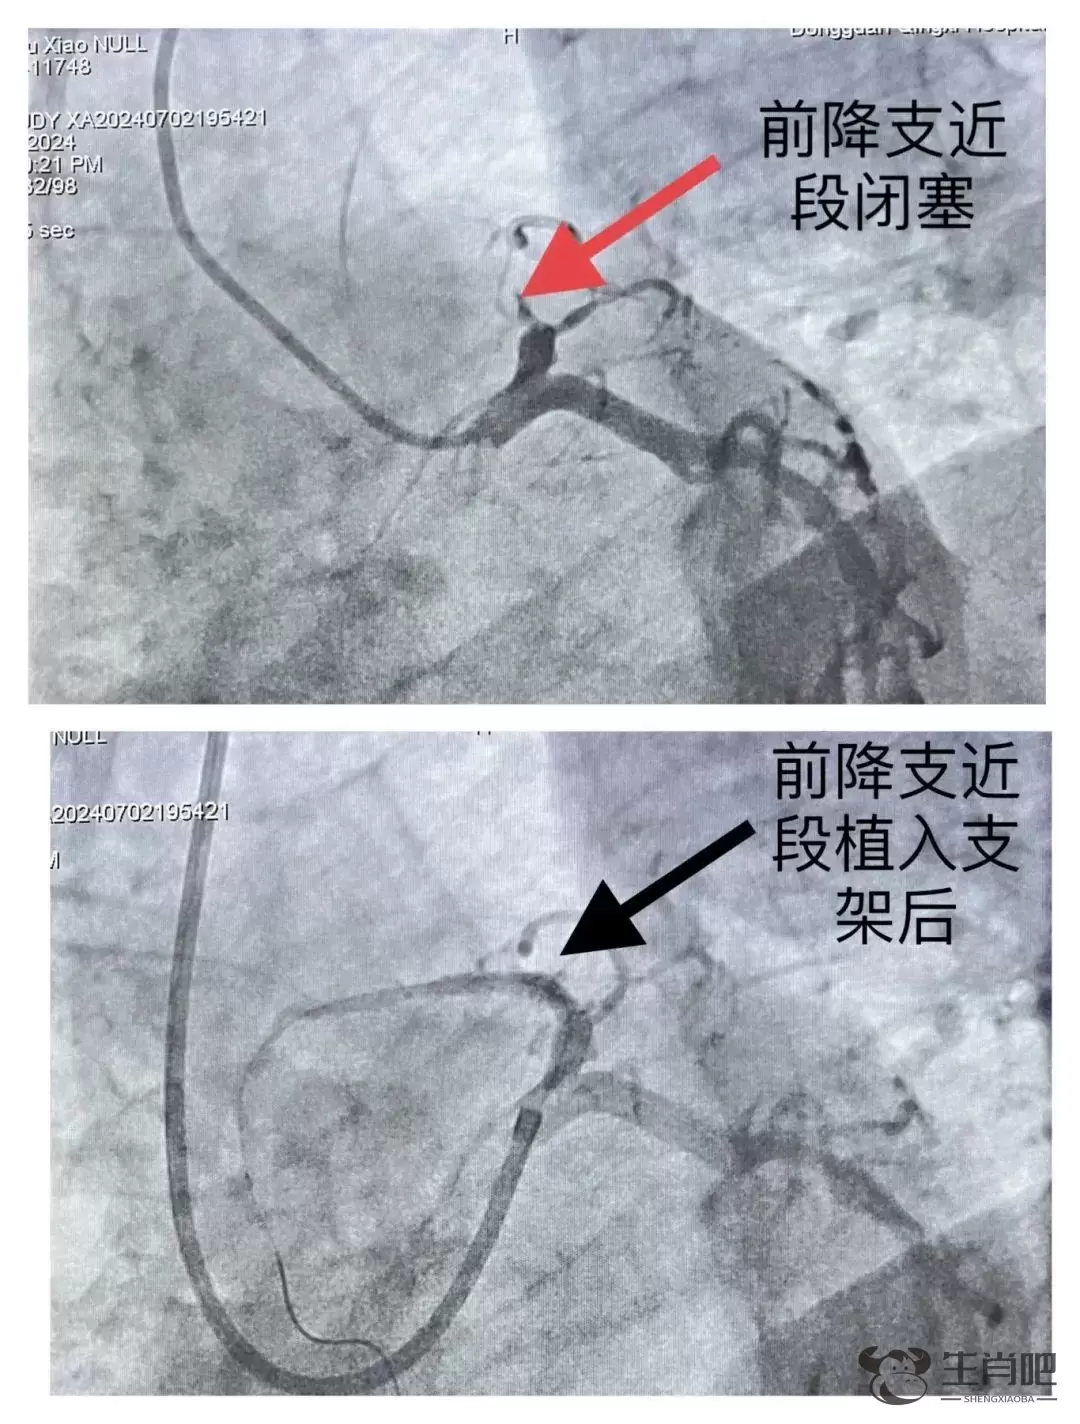

随后实施急诊冠状动脉介入治疗,冠脉造影提示:前降支近段完全堵塞,另外两根血管堵塞了40%到60%。

术中植入支架2枚,复查前降支血流通畅,胸痛缓解,周师傅体内的“炸弹”被解除了。